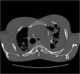

Progressive massive fibrosis (PMF), characterized by the development of large conglomerate masses of dense fibrosis (usually in the upper lung zones), can complicate silicosis and coal worker's pneumoconiosis. Conglomerate masses may also occur in other pneumoconioses, such as talcosis, berylliosis (CBD), kaolin pneumoconiosis, and pneumoconiosis from carbon compounds, such as carbon black, graphite, and oil shale. [Source: Wikipedia ]